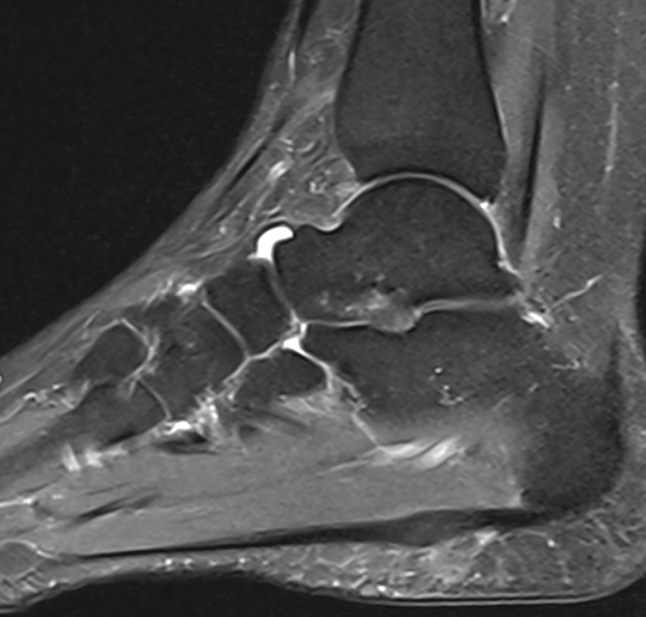

3. Mid plantar fasciitis